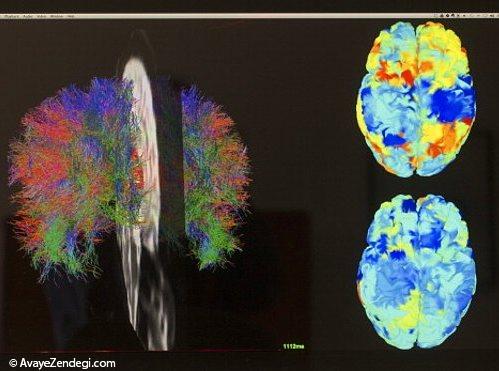

11- 60 درصد از ماده سفید مغز، از میلین ها تشکیل شده که سرعت انتقال پیام الکتریکی را با کمک این ماده سفید، افزایش می دهد.

12- روغن ها به همان اندازه که برای قلب شما مضر هستند، برای کارایی مغز مفید اند. از جمله میلین ها که بیش از نیمی از مغز انسان را تشکیل می دهند از روغن تشکیل شده اند.